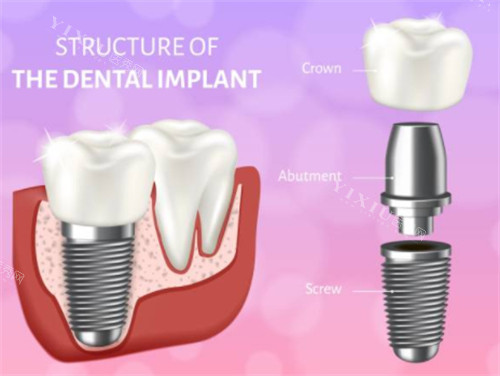

种植牙项目

韩国登腾种植牙:2980元起

韩国奥齿泰种植牙:3800元起

美国皓圣种植牙:4500元起

德国ICX种植牙:5200元起

法国安卓健种植牙:5800元起

瑞士ITI种植牙(亲水型):6500元起

瑞典诺贝尔种植牙(CC):7200元起

瑞典诺贝尔种植牙(Active):7800元起

以色列雅定种植牙:8000元起

意大利BB种植牙:8500元起